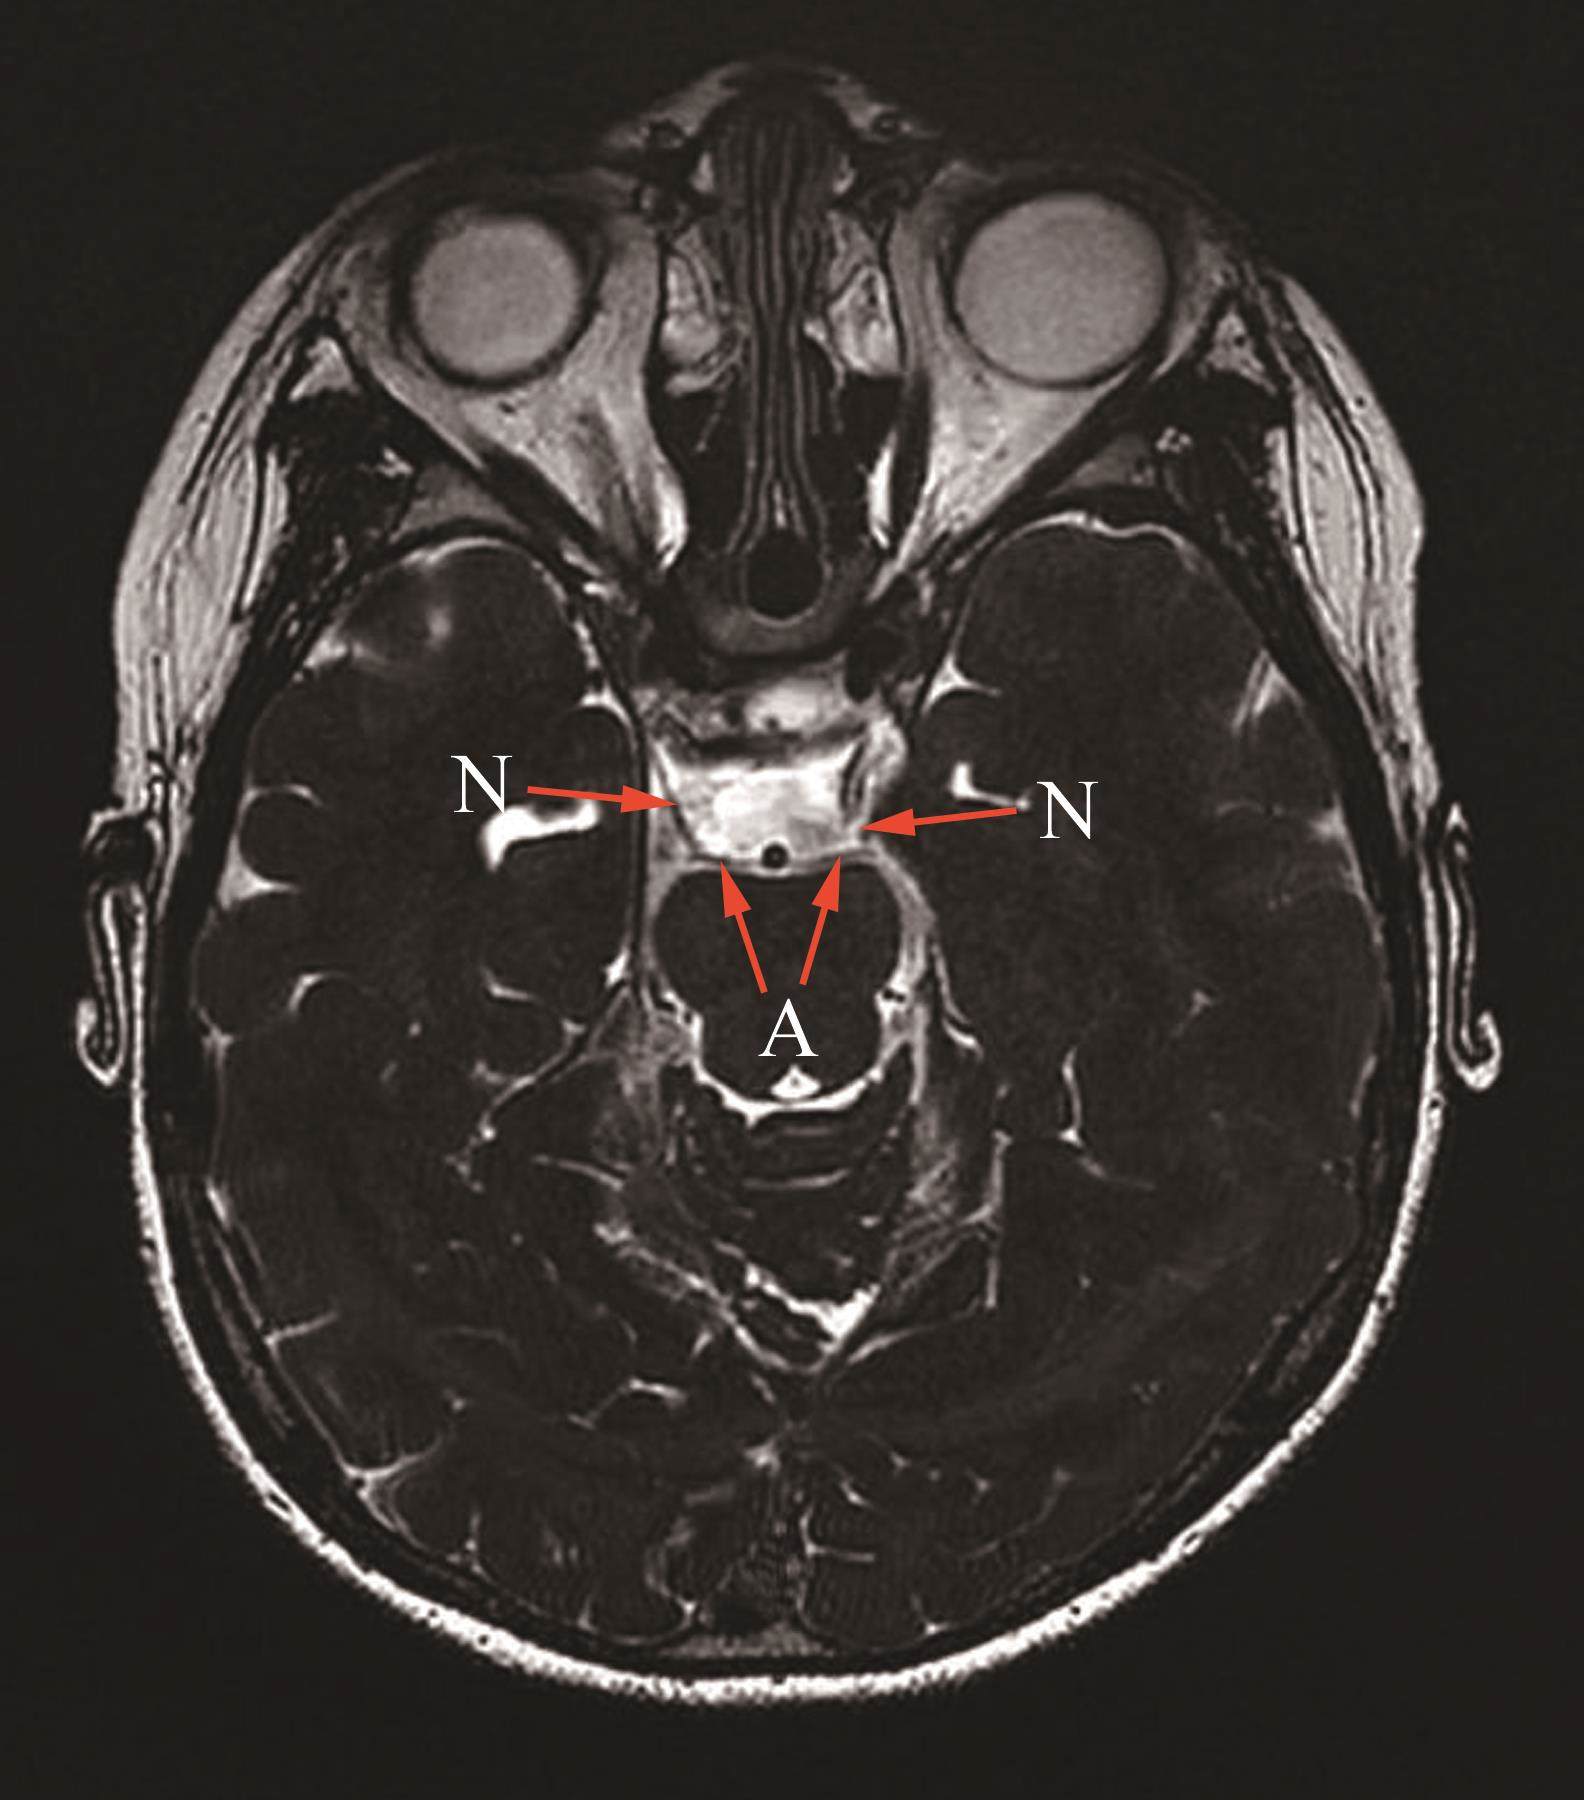

专科检查结果:1)右眼裸眼视力为0.4,左眼裸眼视力为0.8。2)外眼检查示眼睑正常,泪器、泪点正常,附属器正常。3)注视性质为中心注视。4)无代偿头位。5)双眼运动为双眼向上、向下运动减弱(图1)。6)斜视度为L/R 30△。7)右眼上睑下垂(图1C),右眼睑裂高度为4.5 mm,左眼睑裂高度为9 mm;右眼提上睑肌肌力为0,左眼提上睑肌肌力为8,双眼Bell征阴性;右眼瞳孔直径为3~4 mm,左眼瞳孔直径为2.5 mm。8)无眼球震颤。9)主导眼为右眼。10)屈光介质正常。11)眼底未见明显异常。验光结果:右眼+0.75/+1.0*100→0.8;左眼+0.5/+0.5*80→1.0。患儿动眼神经磁共振平扫+增强+水成像(图2)结果示双侧动眼神经脑池段血管接触阳性。

患儿母亲情况:母亲自小左眼眼睑下垂。双眼向上、向下运动明显减弱(图3)。斜视度为R/L 30△。有明显的左眼上睑下垂;右眼睑裂高度为12 mm,左眼睑裂高度为0.5 mm,右眼提上睑肌肌力为9 mm,左眼提上睑肌肌力为0 mm,双眼Bell征为阴性。患儿母亲动眼神经磁共振平扫+增强+水成像(图4)结果示左侧动眼神经较对侧纤细,双侧动眼神经桥前池段血管接触阳性。